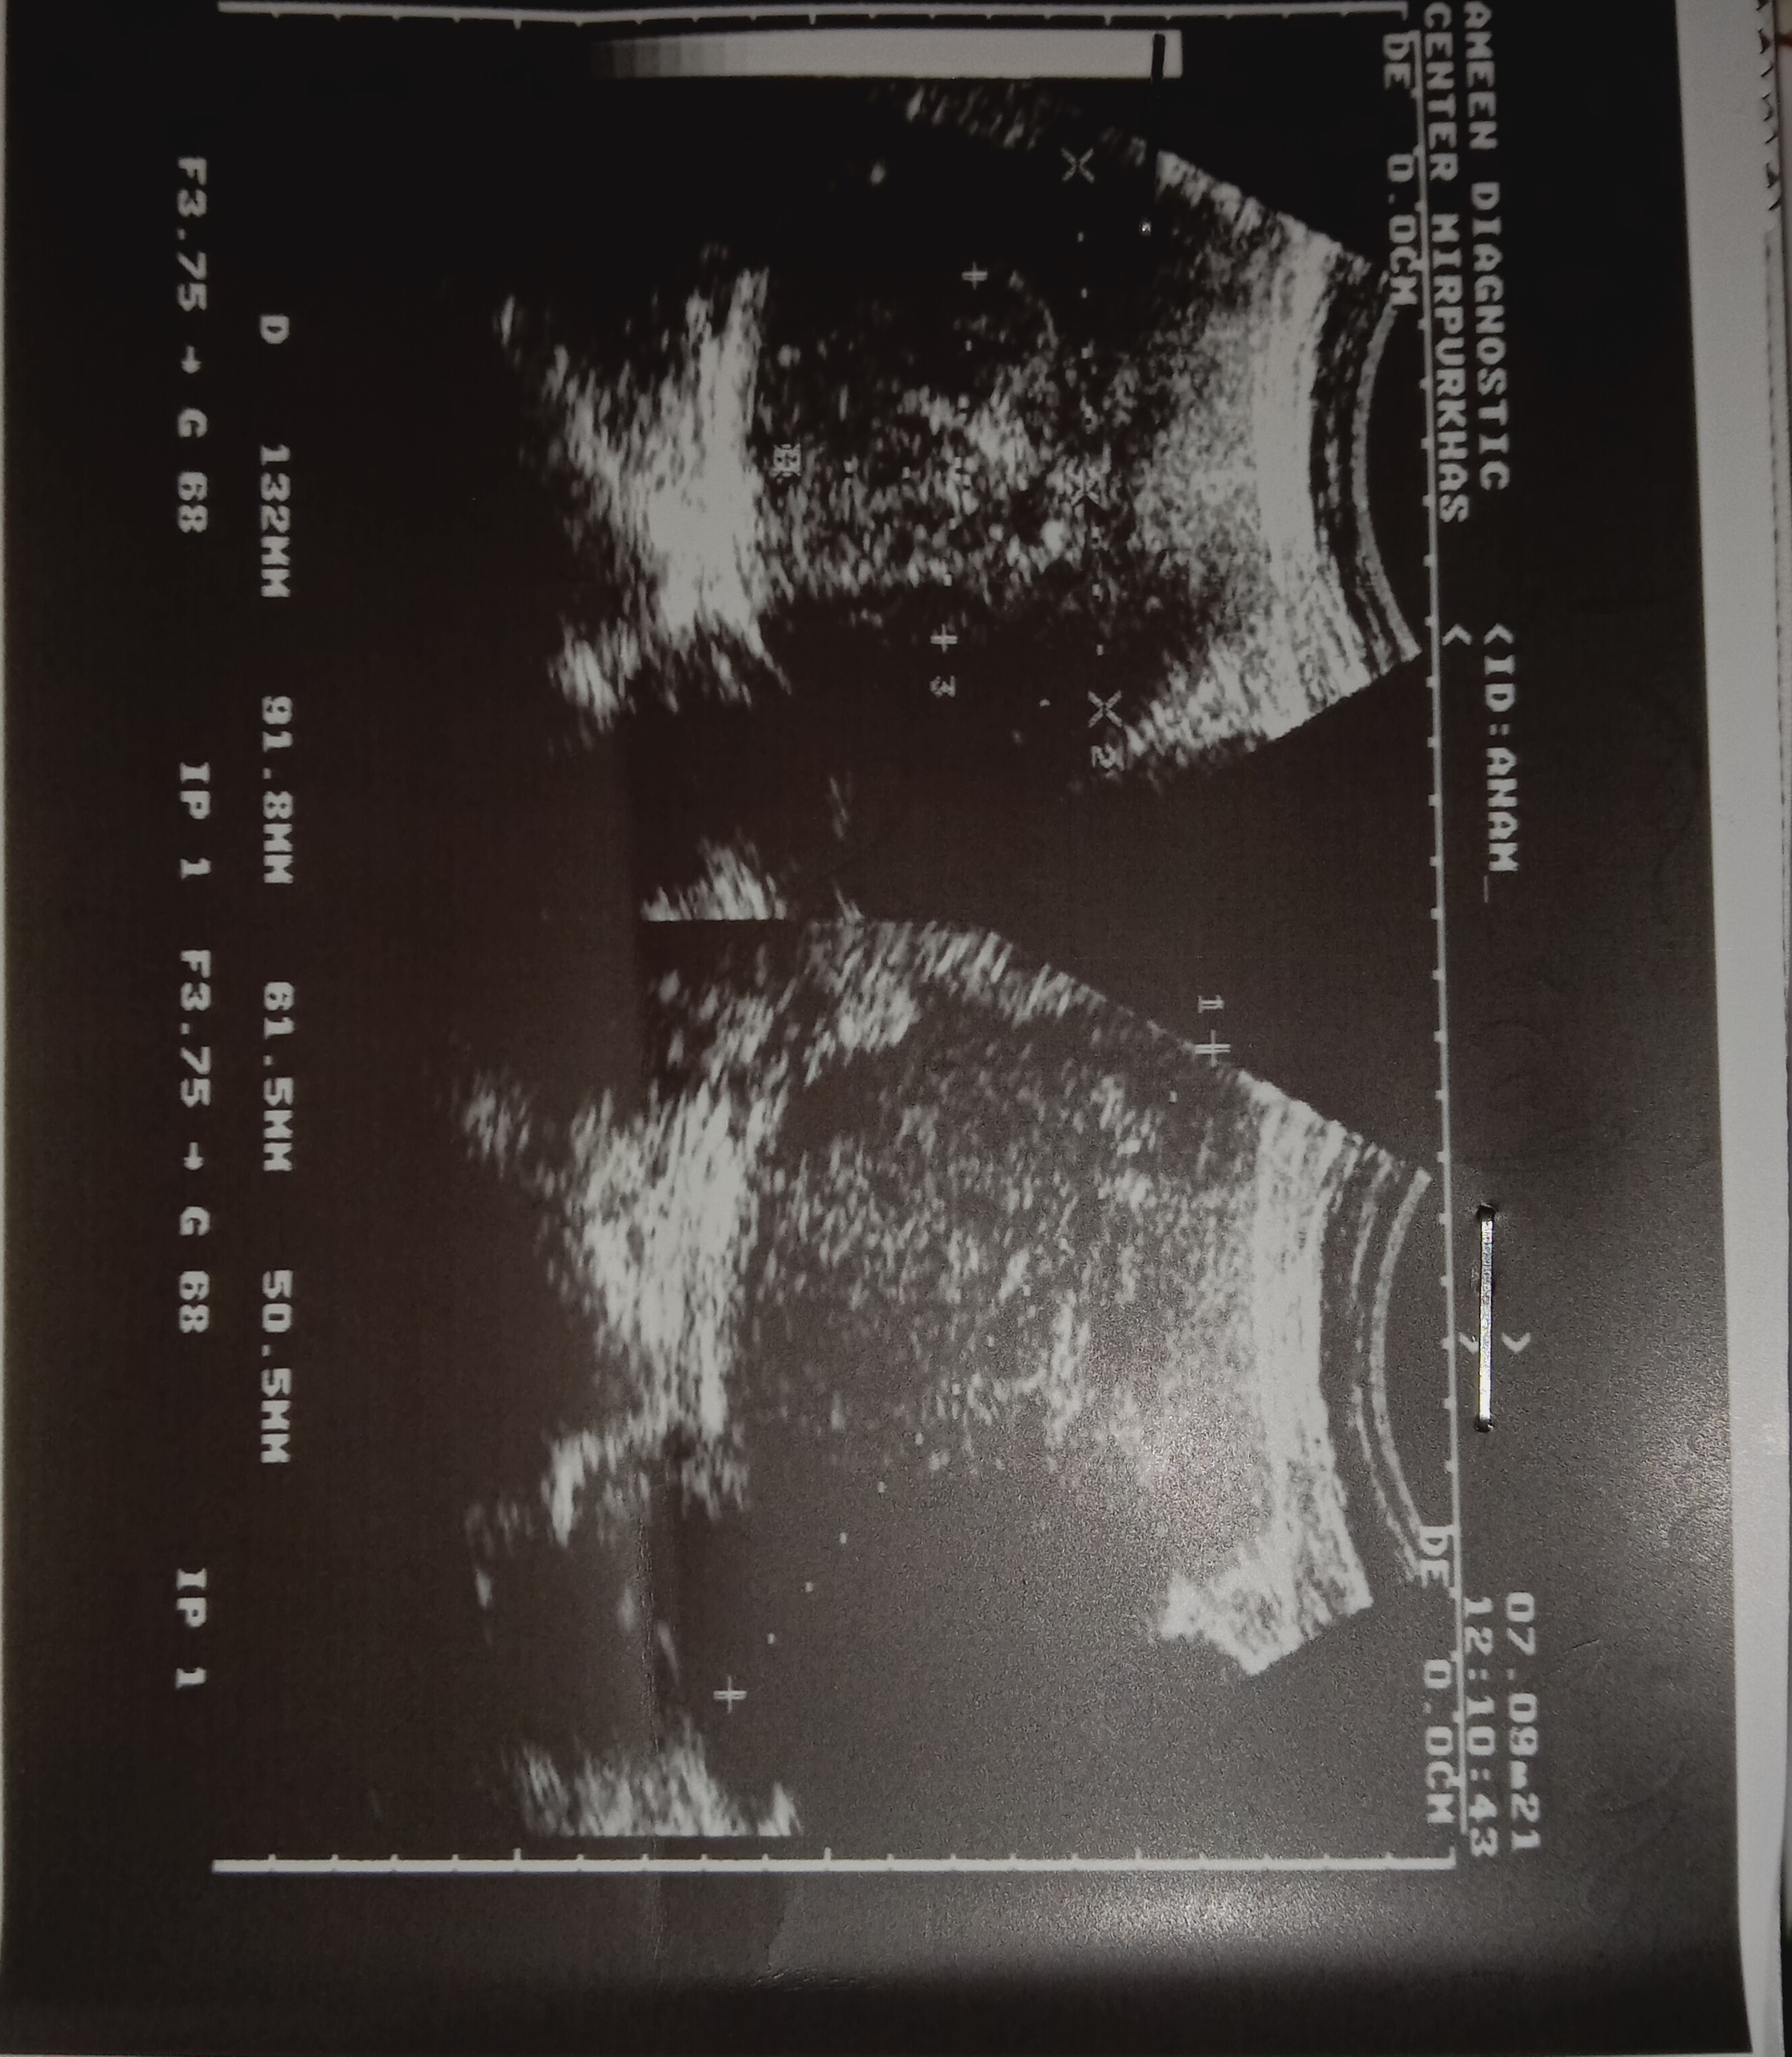

I hava fibroid in my uterous size 6.1 cmand more multiple fibroid uterous lining is 13.2 cm can i get pragnate.

Attach Photo here: